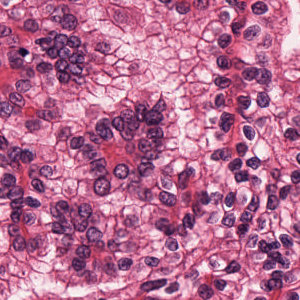

As an essential part of digital pathology, histopathology image analysis is playing increasingly important role in cancer diagnosis, which can provide direct and reliable evidence to diagnose the grade and type of cancer. This paper deals with nuclei segmentation, an important step in histopathological image analysis. The purpose of nuclei semgentation is not only counting the number of nuclei but also obtaining the detailed information of each nucleus. So unlike nuclei detection, here the outputs are the contour of each nucleus instead of only the position of their central points. Hence we can exactly extract each nucleus from the image and make it available for further analysis. For example, the features of the individual nucleus and the distribution of nuclei clusters can be used to grade and classify status of breast cancers [3, 4]. Because of appearance variation such as color, shape, and texture, nuclei segmentation from histopathological images could be very challenging, as illustrated in Fig.1, in which it is very challenging even for human to recognize and segment all nuclei within the images. Fig.1(a) and Fig.1(b) illustrate two histopathological images from different organs. Fig.1(c) and Fig.1(d) are two histopathological images from same organ but have different cancer grade.

H&E stain is the most widely used stain protocol in medical diagnosis. Typically, the nuclei of cells are stained to blue by Haematoxylin while cytoplasm is colored to pink by Eosin. But in practice, the color of H&E stained images could vary a lot due to variation in the H&E reagents, staining process, scanner and the specialist who performs the staining, as shown in Fig.1. A few H&E stain normalization methods[23, 24, 25] have been proposed to eliminate the negative interference caused by color variation. We tried two of them[23, 25] to normalize the raw H&E stained images. For our segmentation algorithm, we did not find any considerable difference between these two normalization methods. Particularly, the result shown in experiment section III is generated based on the images normalized by the method in [23]. Given a target image, this method is able to convert one image’s color into the target image’s color space based on sparse non-negative matrix factorization(NMF). We choose one best stained H&E image as the target and convert other images into its color space. According to the recommendation in [23], the hyper-parameter should be set between 0.01 and 0.1. In our experiment, is set to 0.1.